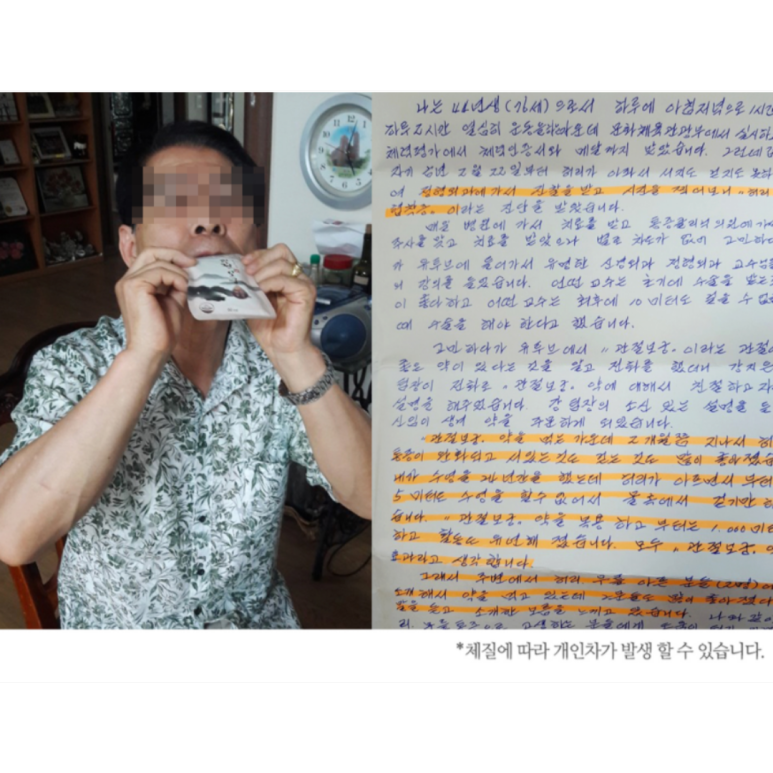

저는 46년생인데 운동을 꾸준히 해 체력인증서도 있을 정도였습니다. 그러나 점점 나이가 들면서 허리협착증 증세가 나타났고 병원에서 진단을 받았습니다.

병원에서 치료를 받고 주사도 맞았는데 나아지질 않아 수술을 해야 한다고 했는데 관절보궁을 알게 되었고 2개월간 복용 했습니다. 결과는 통증이 완화되고 서 있는 것도, 무릎 구부릴때 통증도, 걷는 것도 많이 좋아졌습니다.